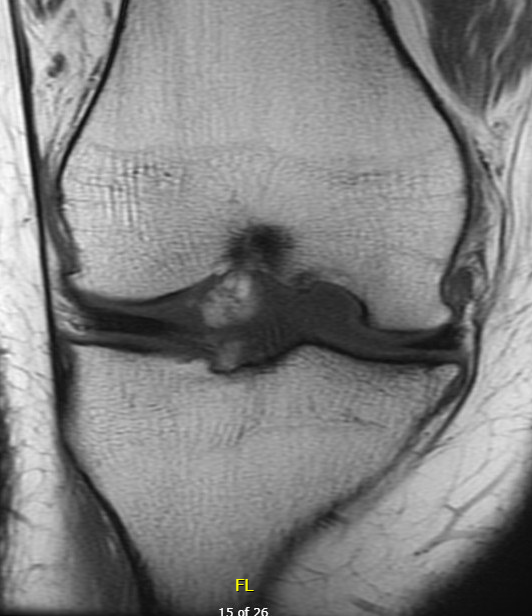

Chondral defect

Osteochondral defect